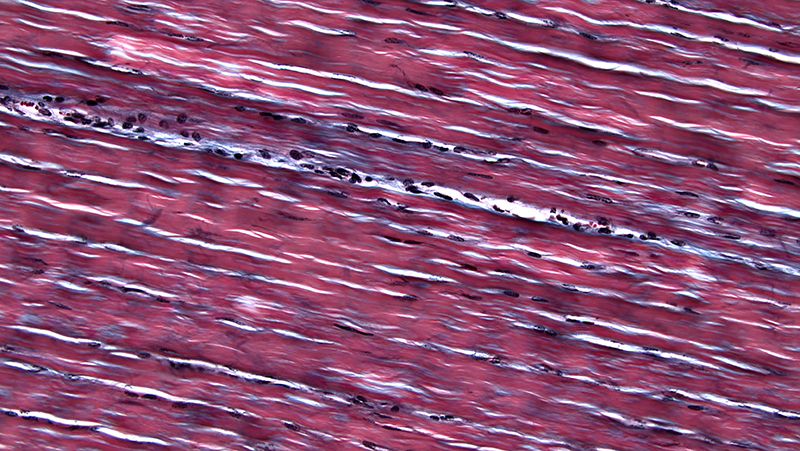

Elastic fiber